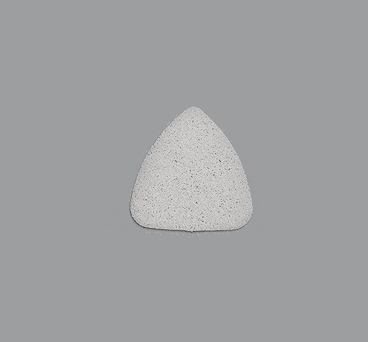

Enophtalmos Wedge